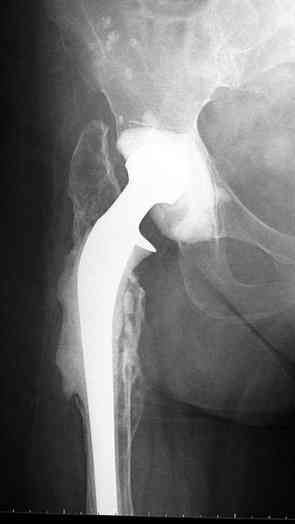

Как-то показывал случай после осложненного тотального эндопротеза,

сперва из-за отсутствия экономических возможности, а затем привыкшая

к своей участи вот уже более 8 лет ходит на временном

"протезе-спейсере".

Полость вертлужной впадины и проксимальное бедро были заполнены

custom made временным протезом из цемента.